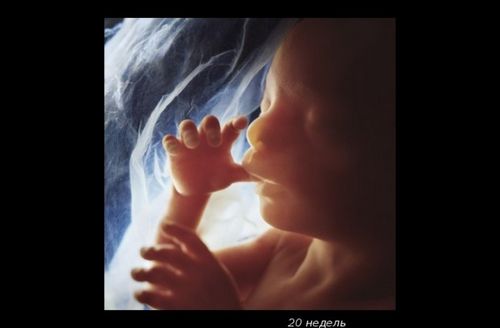

До 20-му тижні вагітності плід виріс до 25 см, виглядає як великий банан. Плід вже повністю сформований, а його тонка шкіра не настільки прозора.

У цей період відбувається знакова подія - дитина почує свою маму - биття її серця, дихання, голос (його окостенілі слухові кісточки тепер здатні проводити звуки). Малюк смокче пальчик, стає більш енергійним.

У кишечнику утворюється первородний кал - меконій і запускаються нирки. На очках чітко видно повіки і вії.